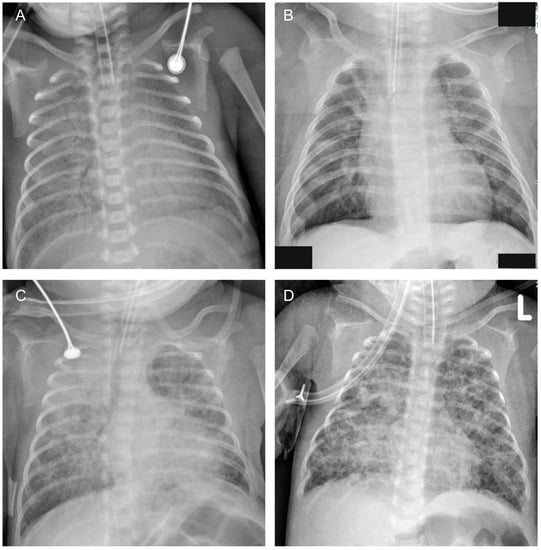

In our NICU, infants had a chest radiograph at their bedside within the first hours of life, and subsequent chest radiographs were performed according to the condition. Chest radiographs obtained within 14 days of life were reviewed for analysis. Four types of images were supposed to be meaningful: (1) diffuse opacities (blurred cardiac and diaphragmatic edge or white lung) on two consecutive chest radiographs within 7 days of life; (2) grid shadows/interstitial opacities; (3) mass opacities; (4) cystic lucencies (Shown in Figure 1). Any one of the above criteria was considered positive.

Figure 1. Chest radiographic images: (A) Diffuse opacities (blurred cardiac and diaphragmatic edge). (B) Grid shadows/interstitial opacities. (C) Mass opacities. (D) Cystic lucencies.

The chest-radiographic images serving as a postnatal predictive factor in our study were easy to identify and achieved a good value. Cystic lucencies, to some extent representative of alveolar growth abnormalities, were recognized as the typical radiographic pattern of BPD. However, this typical appearance was less frequent within the first days of life. As supplementation, we incorporated radiographic signs of diffuse opacities (blurred cardiac and diaphragmatic edge or white lung), grid shadows/interstitial opacities and mass opacities, which could be present ahead of cystic lucencies. With the prevalence of antenatal steroids clinical practice, the incidence and severity of respiratory distress syndrome (RDS) has decreased [24]. An appearance of near or definite white lung on a chest radiograph taken within the first hours of life was correlated with severe RDS or might indicate acute respiratory distress syndrome (ARDS) that did not respond well to single-dose surfactant replacement. ARDS is a common cause of respiratory failure in critically ill patients, resulting in increased morbidity and mortality. Laboratory studies have demonstrated inflammation response resulting in both alveolar epithelial and endothelial injury in ARDS [25]. Infants with ARDS depended on invasive ventilator-assisted and iNO treatments [26]. Considering the physiopathologic mechanism and ventilation mode, ARDS seemed to impose a potential hazard on BPD. Unfortunately, none of the studies assessed the effect of ARDS as an independent risk factor on BPD, probable due to the dilemma of diagnosing ARDS in preterm infants in a definite way. Although a consensus on neonatal ARDS was proposed in 2017, it is still very difficult to distinguish RDS from ARDS within the first three days after birth because RDS could also be a trigger of ARDS, and the time for the diagnosis of ARDS and RDS often overlaps. Empirically, an advancing demand for ventilation parameters is a warning of ARDS. Objectively, a series of chest radiographs could provide meaningful signs for a coarse differentiation. Pure RDS recovered quickly with a clearance on a repetitive chest radiograph, while ARDS remained the same or with aggravated opacities. Grid shadows/interstitial opacities always indicated interstitial lesions, including airway, alveolar wall and pulmonary vascular damages and interstitial edema. Previous studies have demonstrated interstitial changes on a chest radiograph to be a predictor for BPD [27]. In addition, interstitial changes were less influenced by inflation status and were easily noticeable and present earlier than cystic lucencies on chest radiograph. Mass opacities were considered as symbols of lung consolidation, representing an infectious process that caused the alveoli, or air sacs, to fill up with fluid or pus. Infants born very preterm and those who had impaired swallowing mechanisms were at a high risk of infection. The overwhelming inflammation during the infectious process brought devastating damage to the developing lung [28]. Bilateral opacities distributed in perihilar regions with an enlarged cardiac silhouette were common signs of pulmonary edema, induced by hemodynamically significant PDA [29]. The overload of pulmonary fluid can affect lung compliance, gas exchange, pulmonary vasculature and myocardial function, thus increasing the need and duration of mechanical ventilation and oxygen needs [30]. These images all have a pathophysiological basis relevant to lung injuries, as a result of which the interpretation of their predictive values makes sense. This clinic-radiological correlation can help in early diagnosis and prognosis of BPD after birth. In addition, a specific radiograph appearance can also provide a reference for treatment. For example, pulmonary edema might suggest the need for fluid restriction, diuretics application and PDA closure, and cystic lucencies always suggests a higher tidal volume requirement.